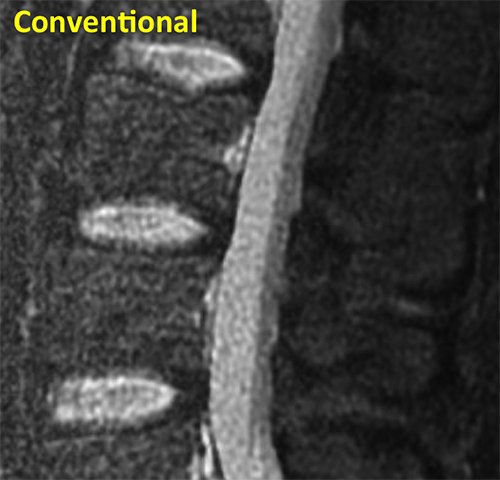

Spine Conventional

This conventional MRI of a spine shows three intervertebral discs with similar signal intensities.